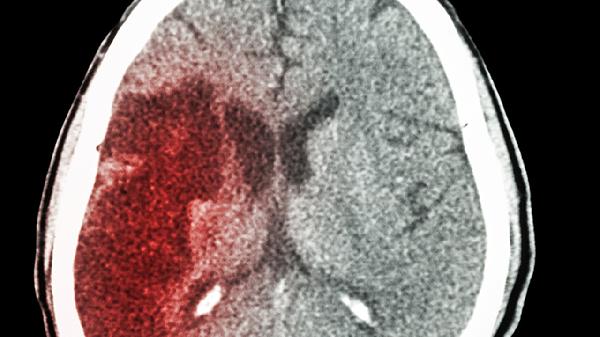

脑梗通常由动脉粥样硬化、心源性栓塞、小动脉闭塞、血液系统疾病以及血管炎或外伤等原因引起。脑梗也称缺血性脑卒中,是由于脑部血液供应障碍导致局部脑组织缺血缺氧性坏死,进而引发神经功能缺损。